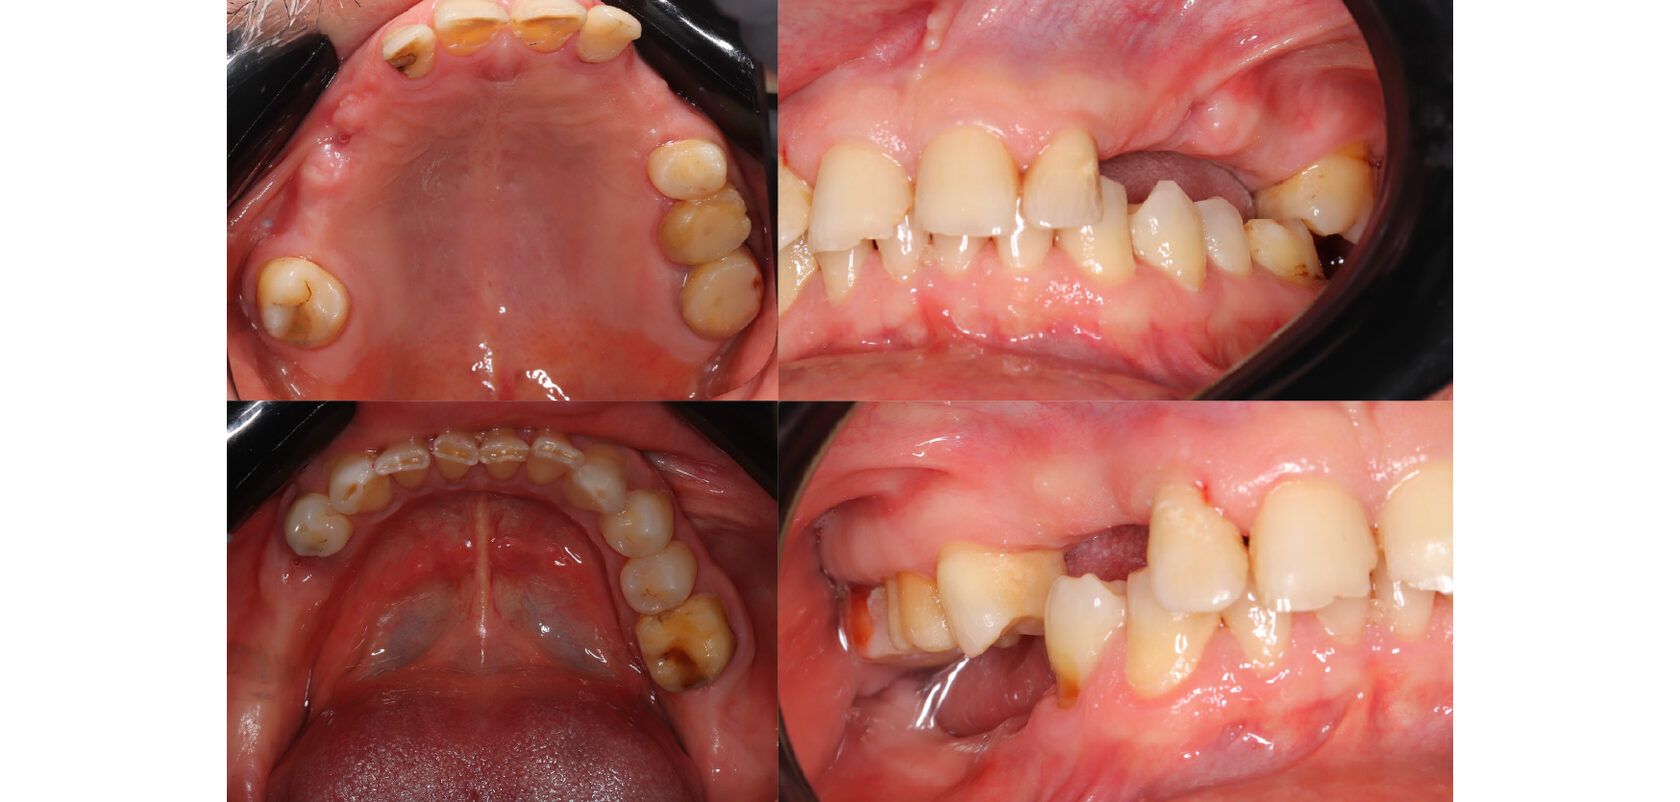

Жалобы пациента на разрушение и отсутствие зубов, желание полноценно жевать и улыбаться. Изначальная ситуация предполагала сначала лечение зубов, которые будут покрываться коронками, а далее уже непосредственно протезирование.

Сначала терапевтом были пролечены и подготовлены к протезированию все оставшиеся зубы. Убран кариес, заменены пломбы и некоторые зубы восстановлены на штифтах. Далее пациент был передан в руки врача ортопеда для протезирования верхней челюсти. Все зубы покрывались коронками и далее изготовился съемный протез.